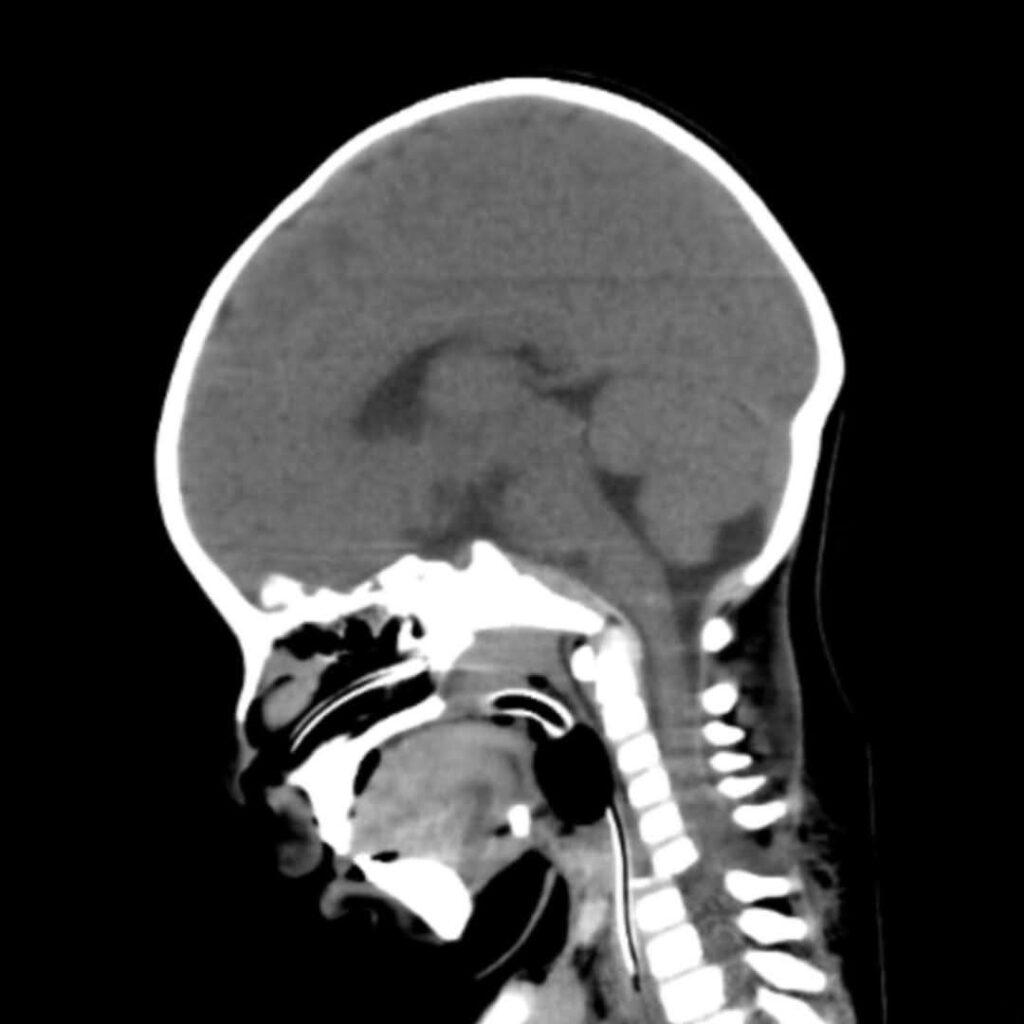

Un bebé de solo 6 meses de edad oriundo de Jujuy fue salvado gracias a una compleja intervención quirúrgica realizada en el CePSI después de sufrir un grave accidente automovilístico.

El pequeño ingresó con politraumatismos severos, incluyendo una luxo fractura cervical, cuadriparesia e inestabilidad hemodinámica.

La cirugía de urgencia fue encabezada por el Dr. Sebastián Sayago, junto con un equipo multidisciplinario del hospital. La operación resultó ser un éxito y logró estabilizar la columna cervical del bebé. Durante su estadía en el CePSI, el paciente fue asistido en la terapia intensiva y logró recuperar la estabilidad hemodinámica y la motricidad en los 4 miembros.